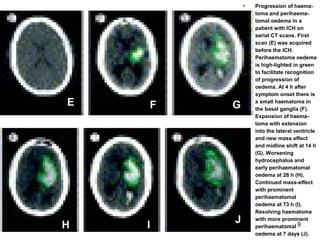

• Progression of haema-

toma and perihaema-

tomal oedema in a

patient with ICH on

serial CT scans. First

scan (E) was acquired

before the ICH.

Perihaematoma oedema

is high-lighted in green

to facilitate recognition

of progression of

oedema. At 4 h after

symptom onset there is

a small haematoma in

the basal ganglia (F).

Expansion of haema-

toma with extension

into the lateral ventricle

and new mass effect

and midline shift at 14 h

(G). Worsening

hydrocephalus and

early perihaematomal

oedema at 28 h (H).

Continued mass-effect

with prominent

perihaematomal

oedema at 73 h (I).

Resolving haematoma

with more prominent

oedema at 7 days (J).